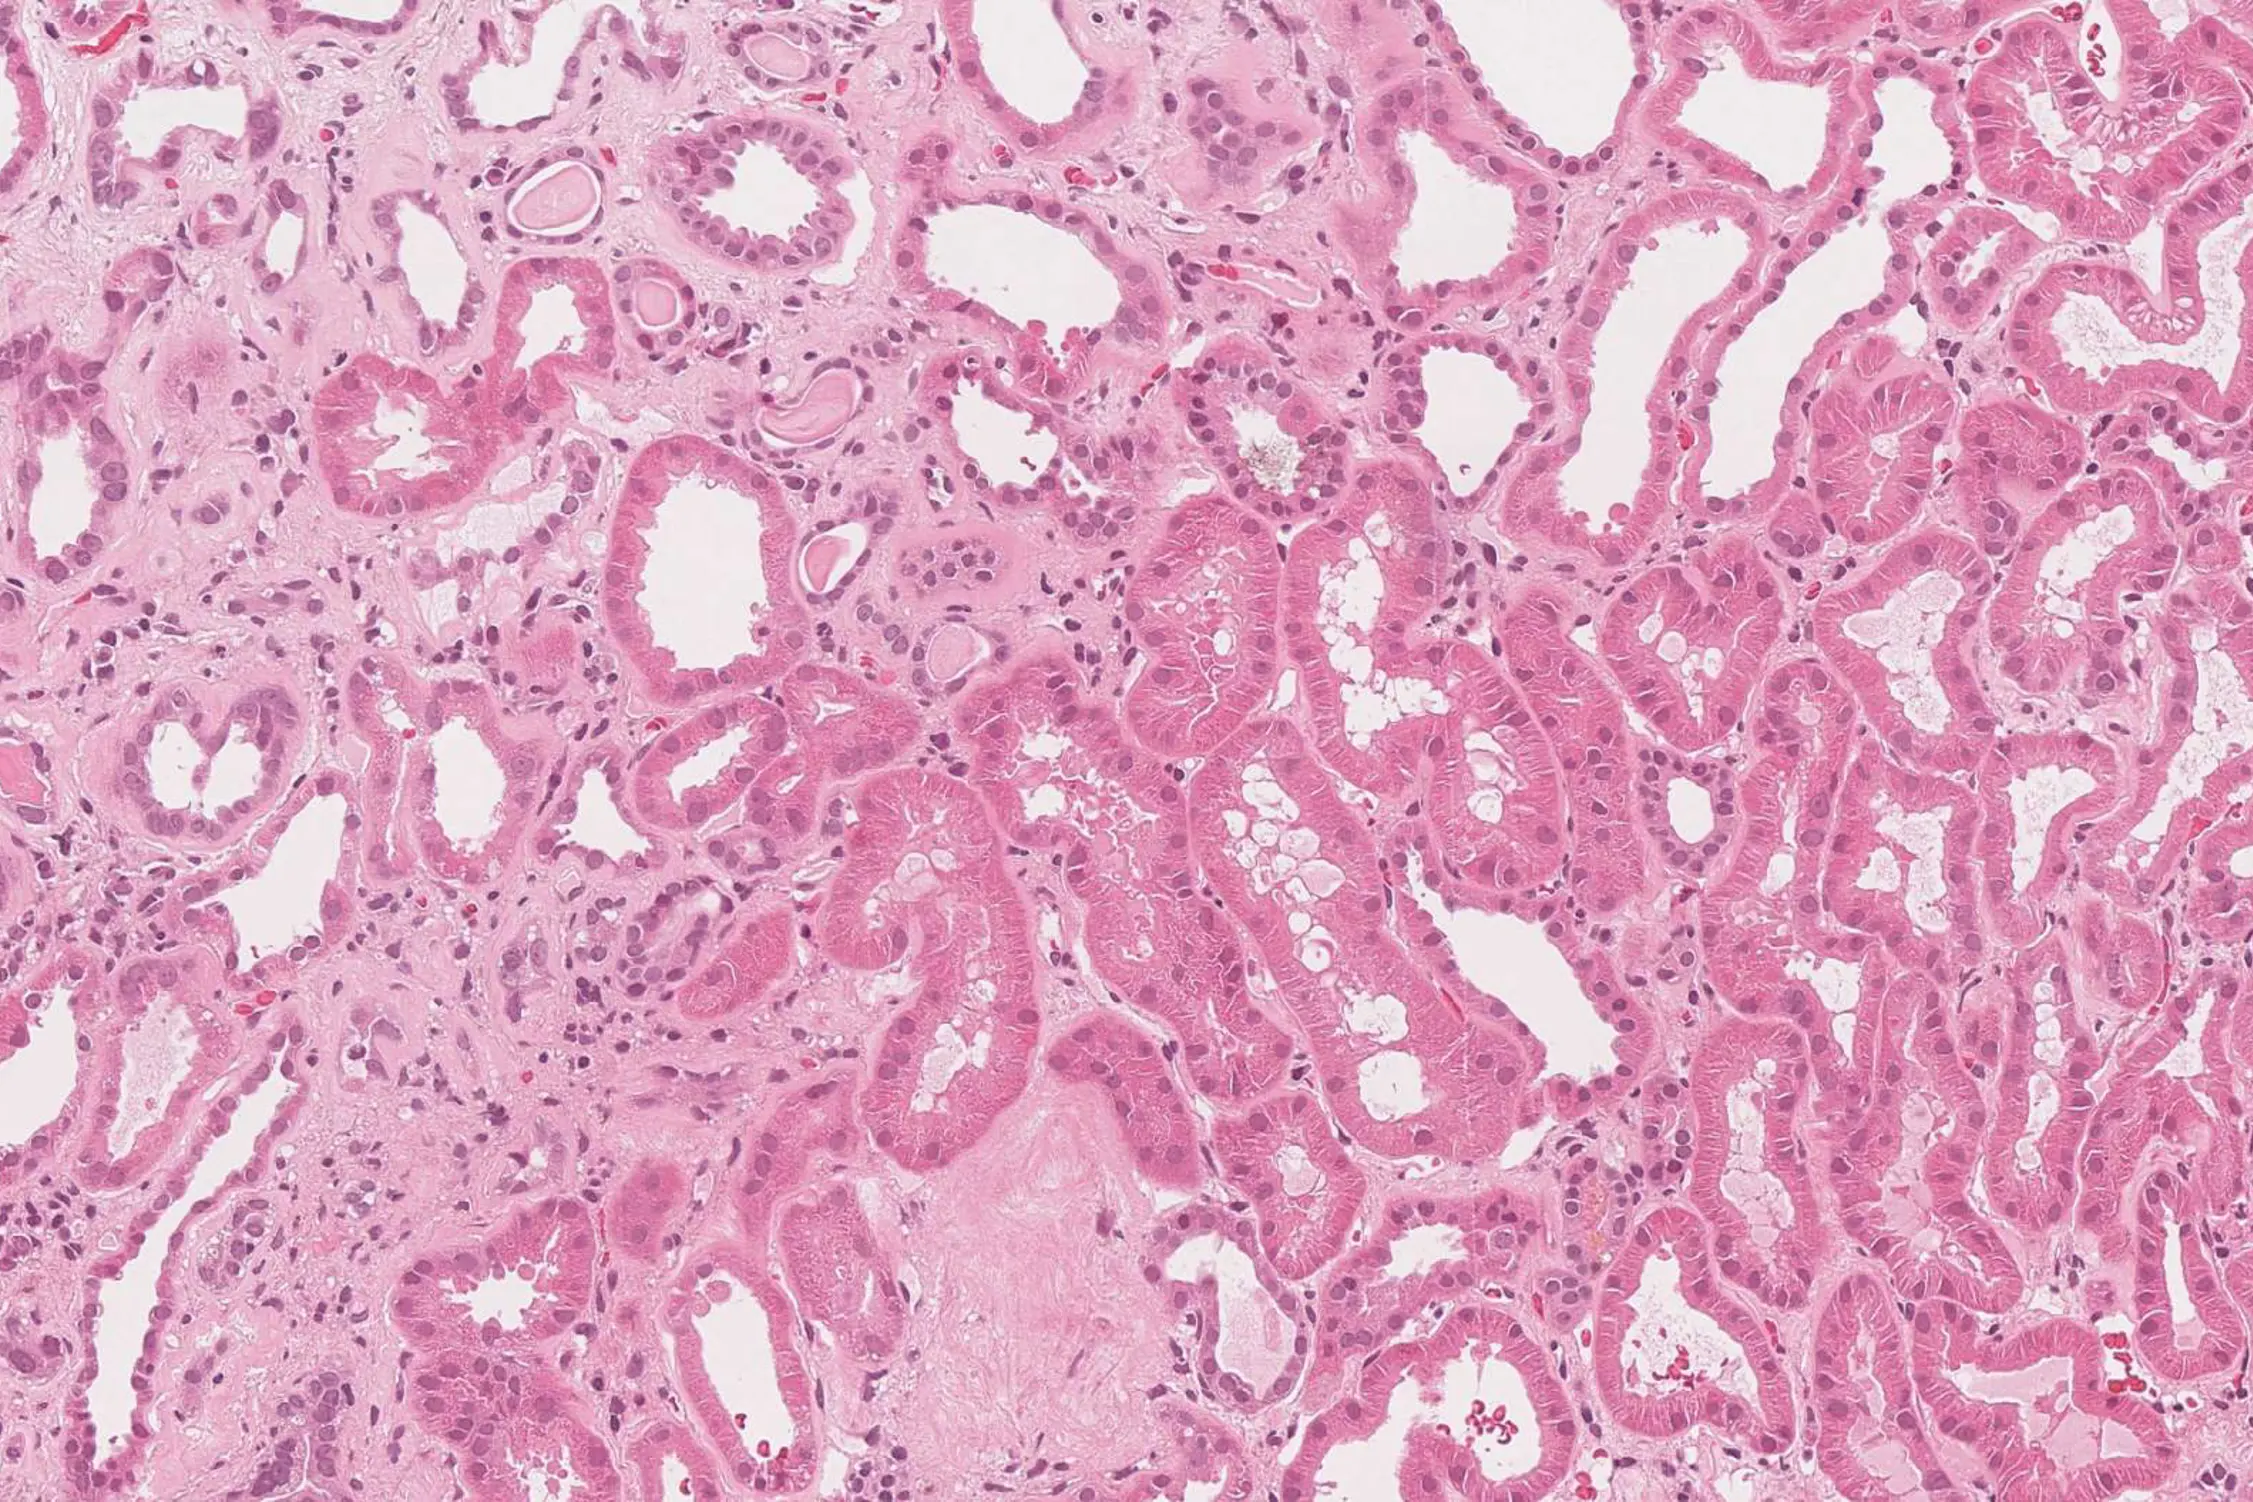

Kidney fibrosis is routinely evaluated by a rough estimate of the extend of fibrotic areas (slight,moderate, severe). This is difficult in routinely hematoxylin-eosin stained sections, because fibrosis is only weakly stained. The image below illustrates this: There is severe fibrosis in the left part and slight fibrosis in the right part.